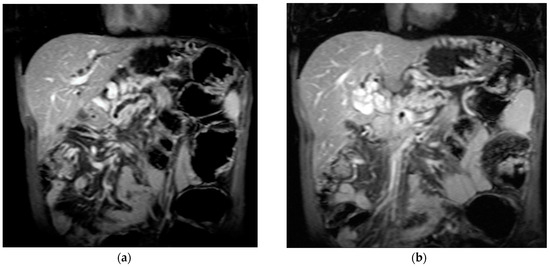

Figure 4.

MRI scan in a patient with pancreatic carcinoma. (a) Enlarged portal vein, with intraluminal thrombus. (b) A hilar 5.1/3.3 cm portal cavernoma.

Transabdominal ultrasound with Doppler protocol (Figure 1a,b and Figure 2a,b), CT scan (Figure 3a,b), and MRI (Figure 4a,b) were used for the diagnosis in 88.9, 75.1, and 15% of cases, respectively. CEUS was used for the diagnosis in 49 cases (25.9%) but in only 29 cases was it used for the evaluation of the thrombus, and in two cases for cavernoma diagnosis (Figure 5a,b and Figure 6a,b).